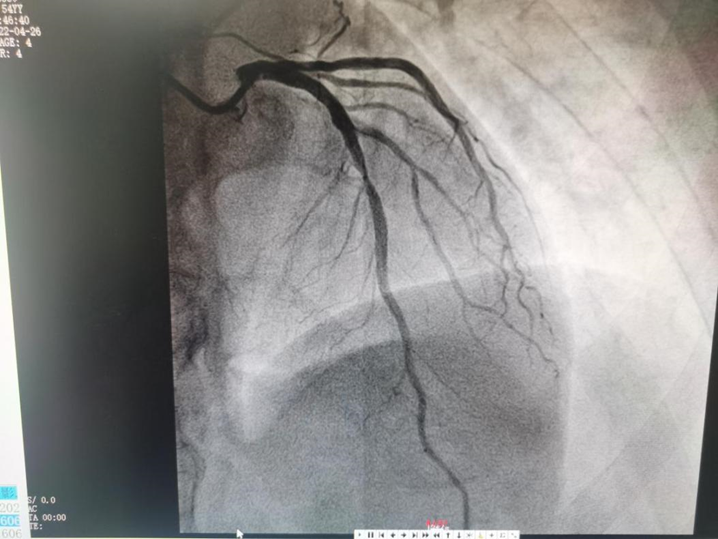

患者林叔已经反复胸闷、胸痛5天了,随着症状逐渐加重,考虑为急性冠脉综合症。术中造影结果显示,林叔前降支近中段存在明显狭窄,LAD弥漫斑块浸润,近段狭窄20%,近中段局限偏心狭窄90%,需要进行介入手术治疗。

▲ 患者前降支造影(术前)